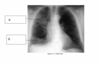

What is shown on the image?

phrenic nerve paralysis